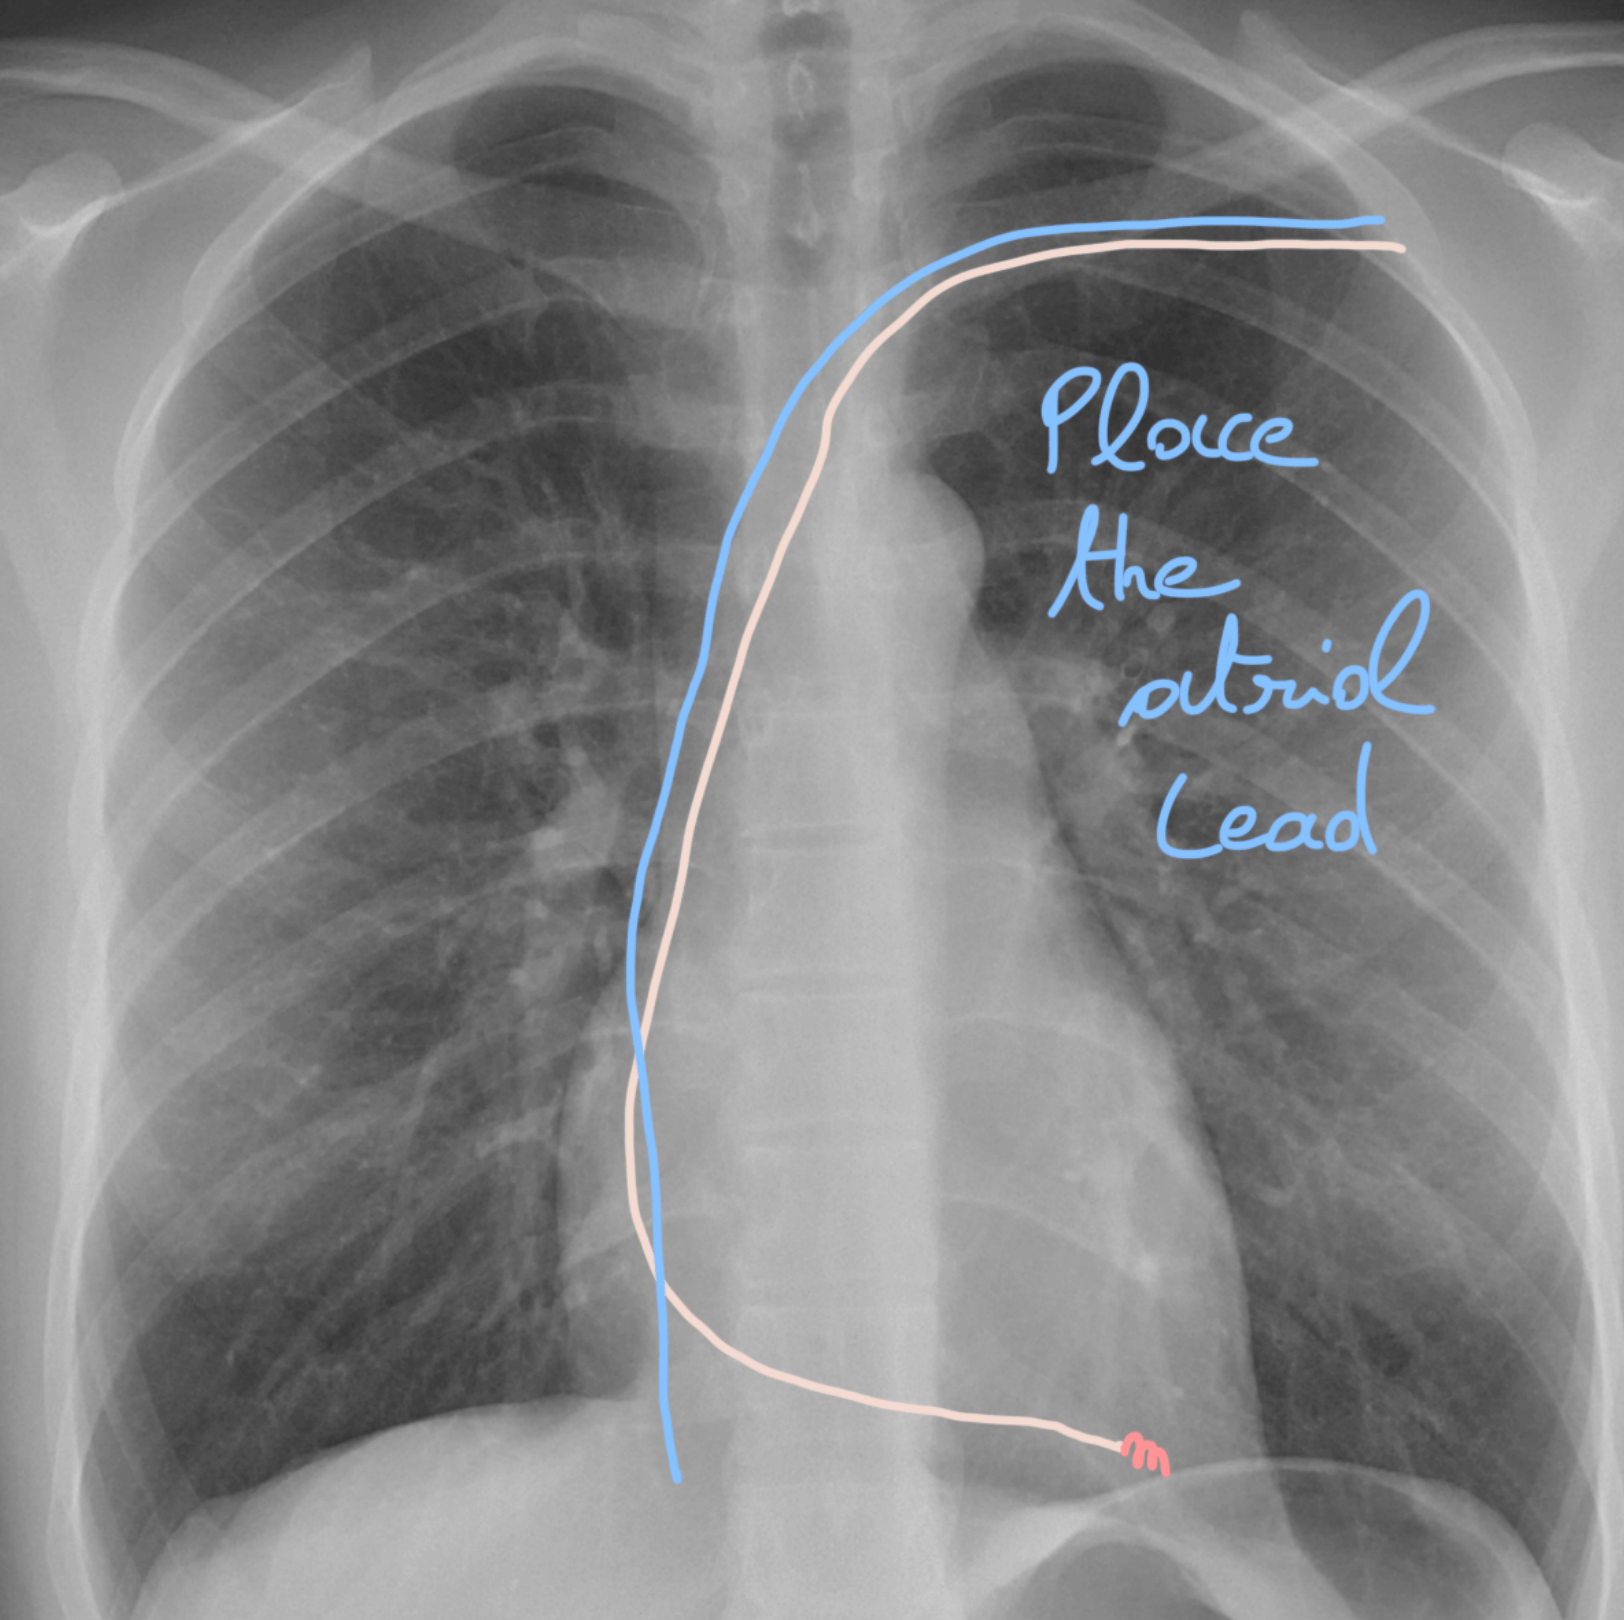

๐ŸŽฏ Step 20: Time for the atrial lead! ๐Ÿชก๐Ÿ’ซ

Now itโ€™s the atrial leadโ€™s turn. First, guide it into the inferior vena cava โฌ‡๏ธ๐Ÿซ, then introduce the dedicated atrial stylet๐ŸŽฉ.

๐ŸŽฃ Step 21: Hook the right atrial appendage! ๐Ÿชก๐Ÿ’ซ

With the atrial stylet, your lead will take on a hook shape.

๐Ÿ‘‰ The goal? To catch the right atrial appendage (RAA) ๐Ÿซ€ like a skilled fisherman reeling in the perfect catch ๐ŸŸ.

๐ŸŒ€ Step 22: Catch & screw the atrial lead! ๐ŸŽฏ

This part gets a bit more technical โ€” so hang on! ๐Ÿ’ช

๐Ÿ‘‰ Gently pull on the atrial lead until you โ€œcatchโ€ the RAA ๐ŸŽฃ.

Youโ€™ll notice the lead will start to horizontalize ๐Ÿ“ โ€” thatโ€™s your signal!

โœ… As soon as itโ€™s horizontal, itโ€™s time to screw it in ๐Ÿ”ฉ to secure the position.